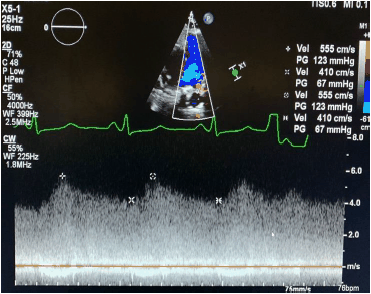

Uma gestante de 18 anos se apresenta para avaliação de sopro.

O sinal de fluxo registrado na imagem a seguir é compatível com

Uma gestante de 18 anos se apresenta para avaliação de sopro.

O sinal de fluxo registrado na imagem a seguir é compatível com